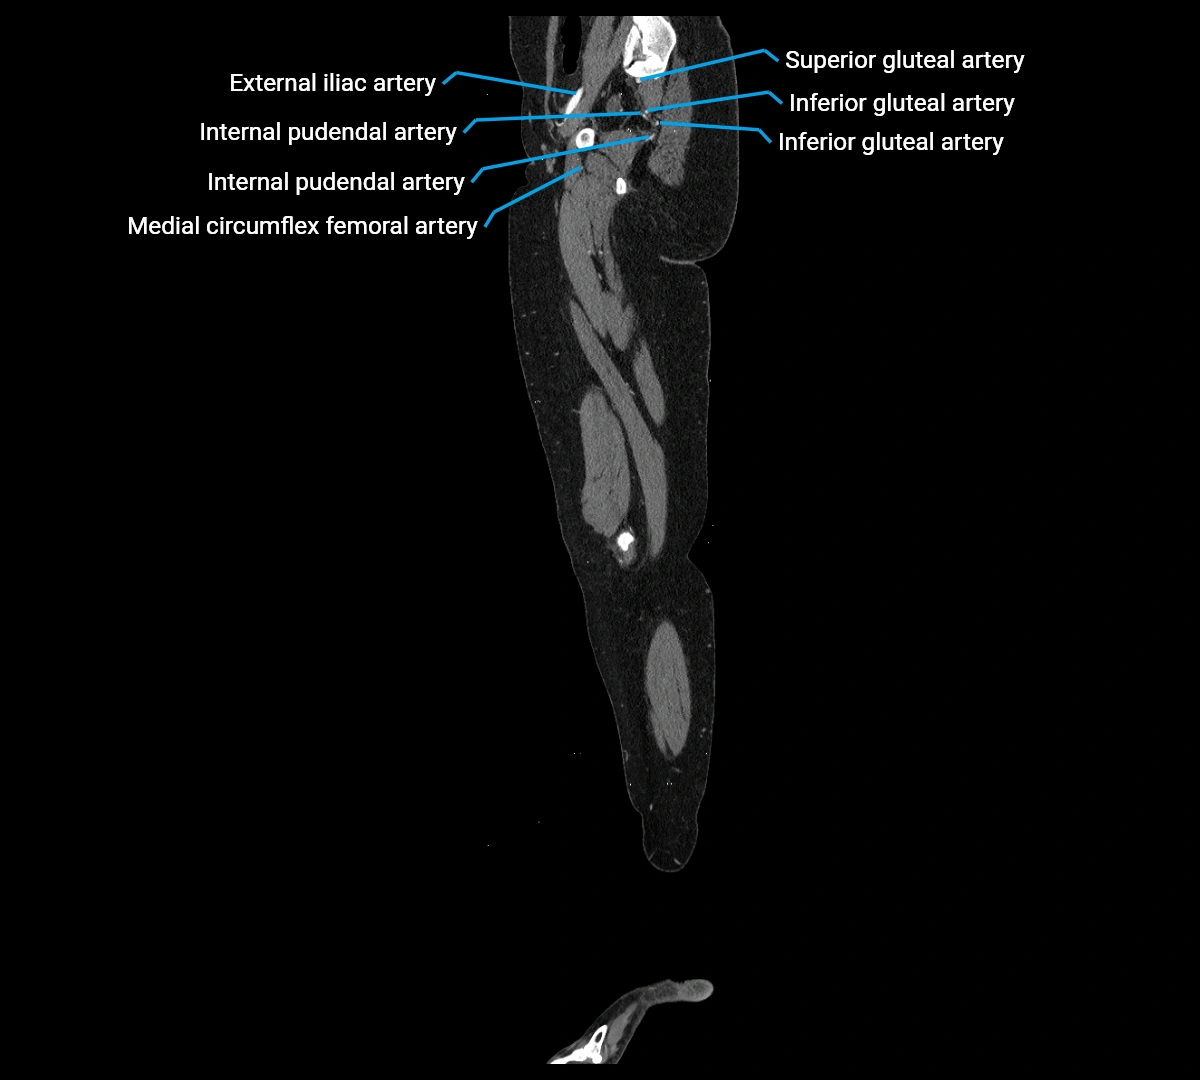

CT images

image